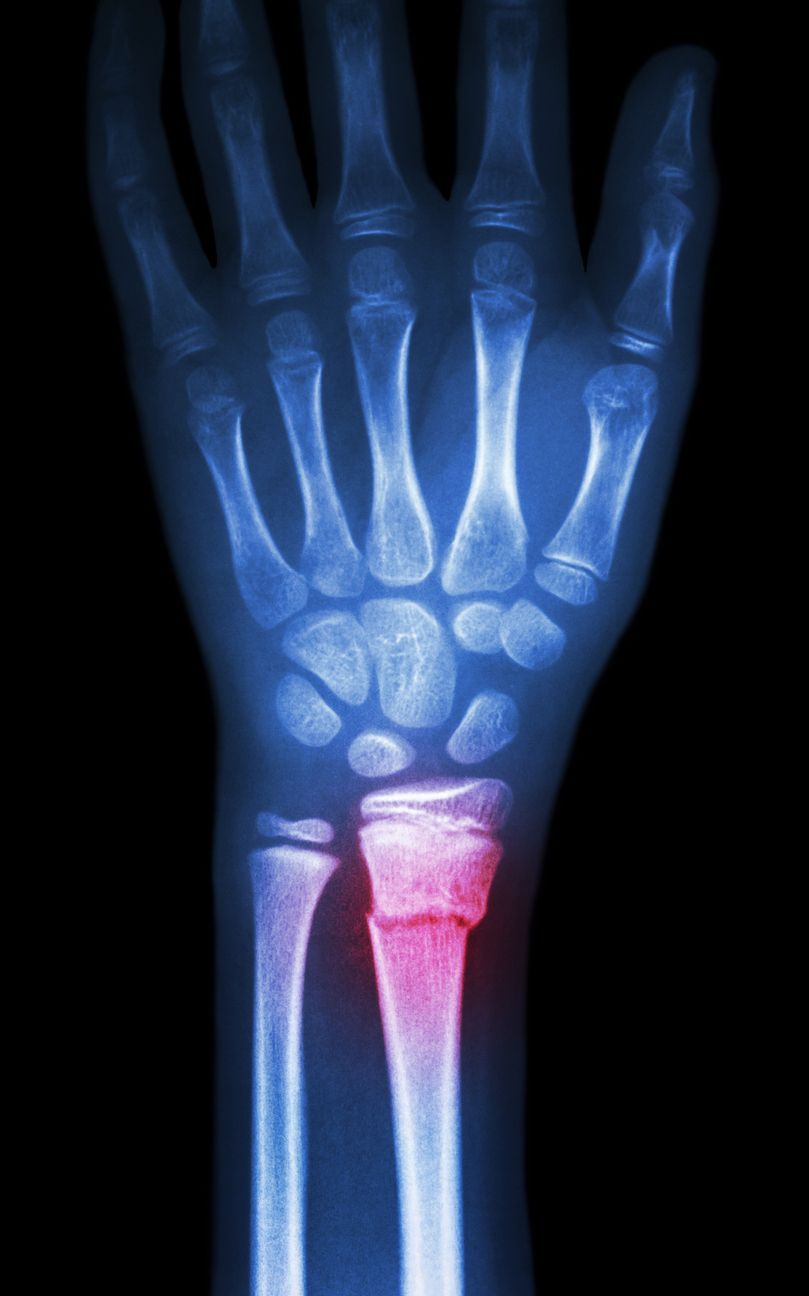

The hand and wrist has 27 individual bones 8 of which form the wrist which articulates with the radius to form the radoiocarpal joint. While the ulna traverses alongside the ulna down towards the wrist, it does not articulate with the bones of the wrist directly, and has a small piece of cartilage known as the triangular fibrocartilage complex (TFCC).

While the hand can perform numbers of very definite and intricate movements as a result of the many bones within the hand and wrist, there is significant ligamentous support between them. These structures, as well as the integrity of the bone, can be at risk when falling on an outstretched hand which can result in joint instability or fracture respectively.